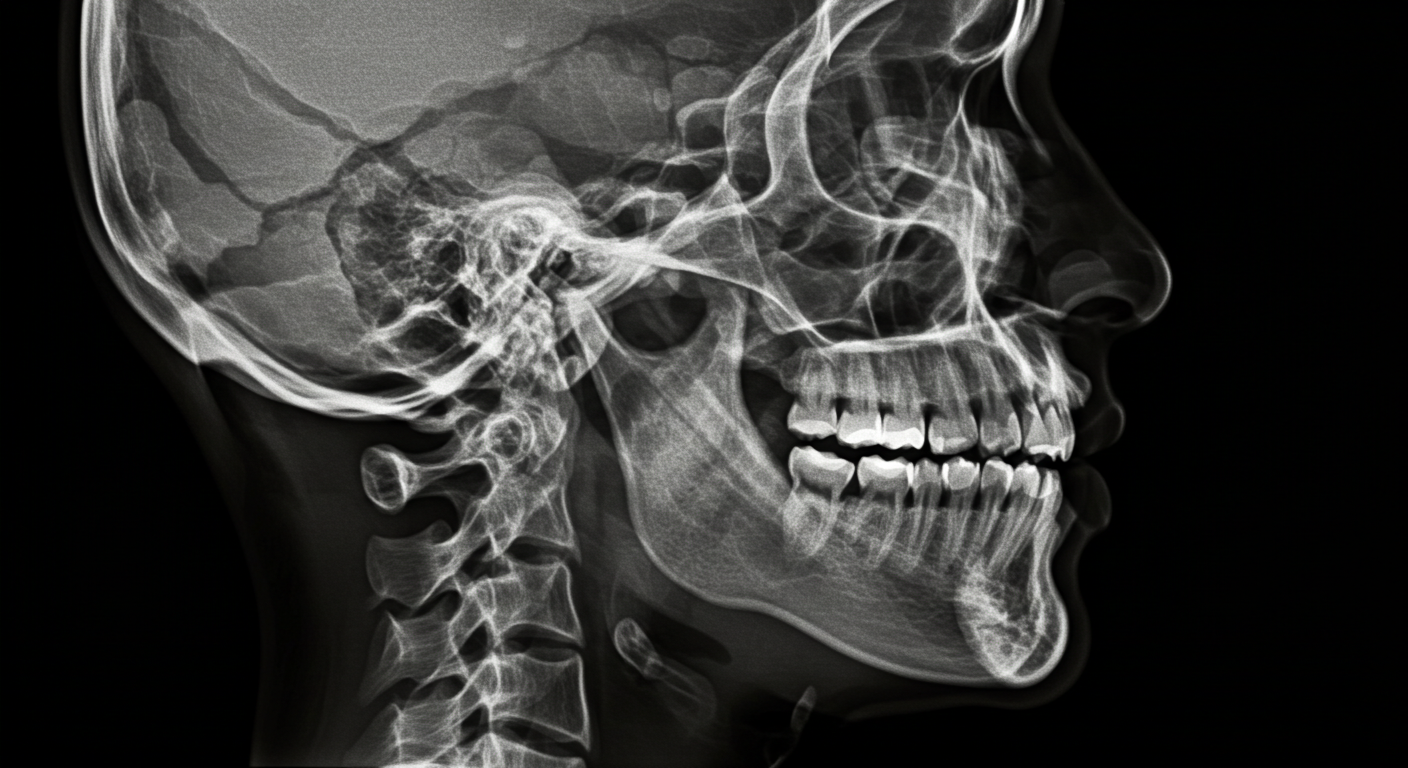

ジンデ歯科口腔外科は、口腔外科を中心とした専門性の高い診療を提供しています。院長は日本口腔外科学会専門医であり、親知らずの抜歯や顎関節症、口腔内の外傷治療など幅広い症例に対応しています。また、最新の歯科用CTを導入し、三次元的な正確な診断による安心・安全な治療を心がけています。

たとえば、埋まっている親知らずの抜歯では、CTによる精密な画像診断を行い、神経や血管の位置を把握した上で、安全に手術を進めます。顎関節症についても、症状や原因を丁寧に見極め、最適な治療方法を提案しています。さらに、事故やスポーツによる口の中の裂傷や骨折にも迅速に対応できる体制を整えています。

診断には、必要に応じてレントゲン撮影や歯科用CTを活用し、目に見えない部分の虫歯も正確に把握します。治療の際には、痛みを最小限に抑えるよう配慮しながら進めますので、不安な点があれば遠慮なくご相談ください。

治療では、まずCTによる精密な検査を行い、顎の骨の状態や神経・血管の位置を正確に把握します。専用のシミュレーションソフトを使って、インプラントの埋入位置や角度、深さなどを詳細に計画し、必要に応じてサージカルテンプレートを作製します。これにより、従来よりも短時間で正確な手術が可能となり、より安全性の高い治療を実現しています。